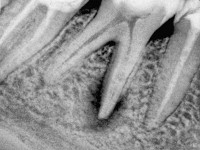

Расширения периодонтальной щели или деструкции костной ткани при серозном периодонтите на рентгенограмме не обнаруживают. Если причиной инфицирования периапикального периодонта является недопломбировка каналов или, наоборот, выведение материала за границы апекса, прицельный рентгеновский снимок необходим для установления этиологии заболевания и выбора рационального плана лечения. При серозном периодонтите показатели ЭОД варьируют в диапазоне от 100 мкА и выше, что свидетельствует о распаде пульпы. Термопроба отрицательная.